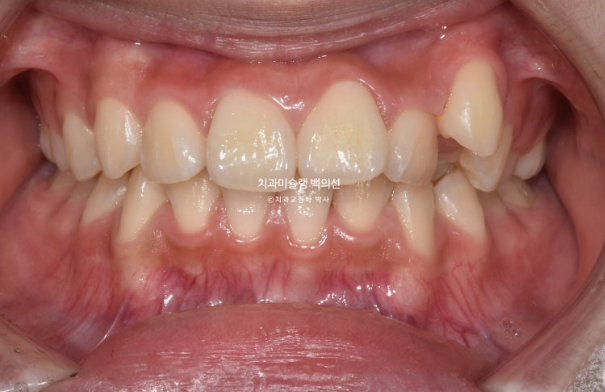

23년 2월 교정치료를 위해 온 중학생 환자분입니다.

덧니와 중심선 불일치, 과개교합 등이 눈에 띕니다.

덧니가 있으면 덧니쪽으로 중심선이 돌아가게 됩니다.

교정치료로 치아중심선을 코와 인중에 맞춰야 합니다.

앞니 뻗침도 있어서 약간의 돌출입도 있습니다.

덧니와 돌출 해소를 위해 작은어금니 발치교정이 필요합니다.

단 위에만 2개 발치 치료계획을 세워습니다.

아래 작은어금니까지 총 4개를 빼면 입이 너무 많이 들어가게 되기 때문입니다.

클리피씨 교정 선택하셨고 치료 들어갔습니다.